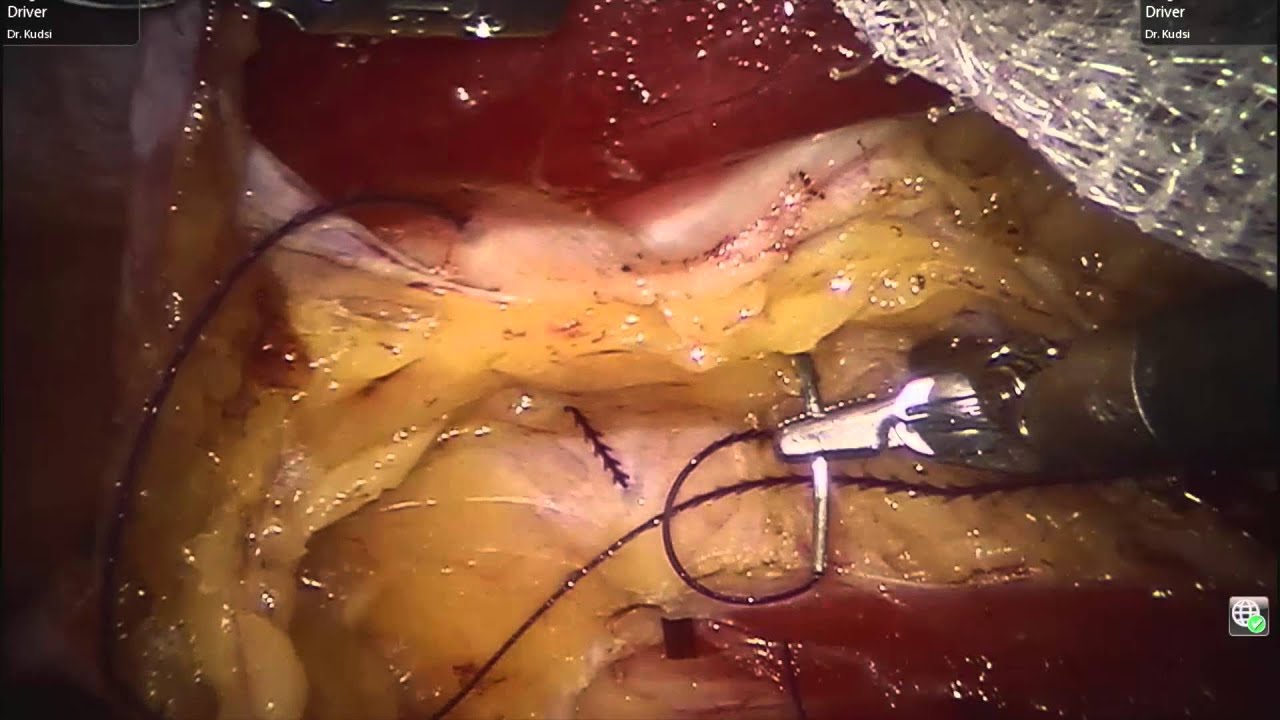

robotic surgery disadvantages Robotic Inguinal Hernia Repair (r-TAPP).

video phone beyonce mp3 Robotic Bilateral Inguinal Hernia Repair

video phone beyonce mp3 TAPP -- Robotic Inguinal / Femoral Hernia Repair with mesh (Progrip)